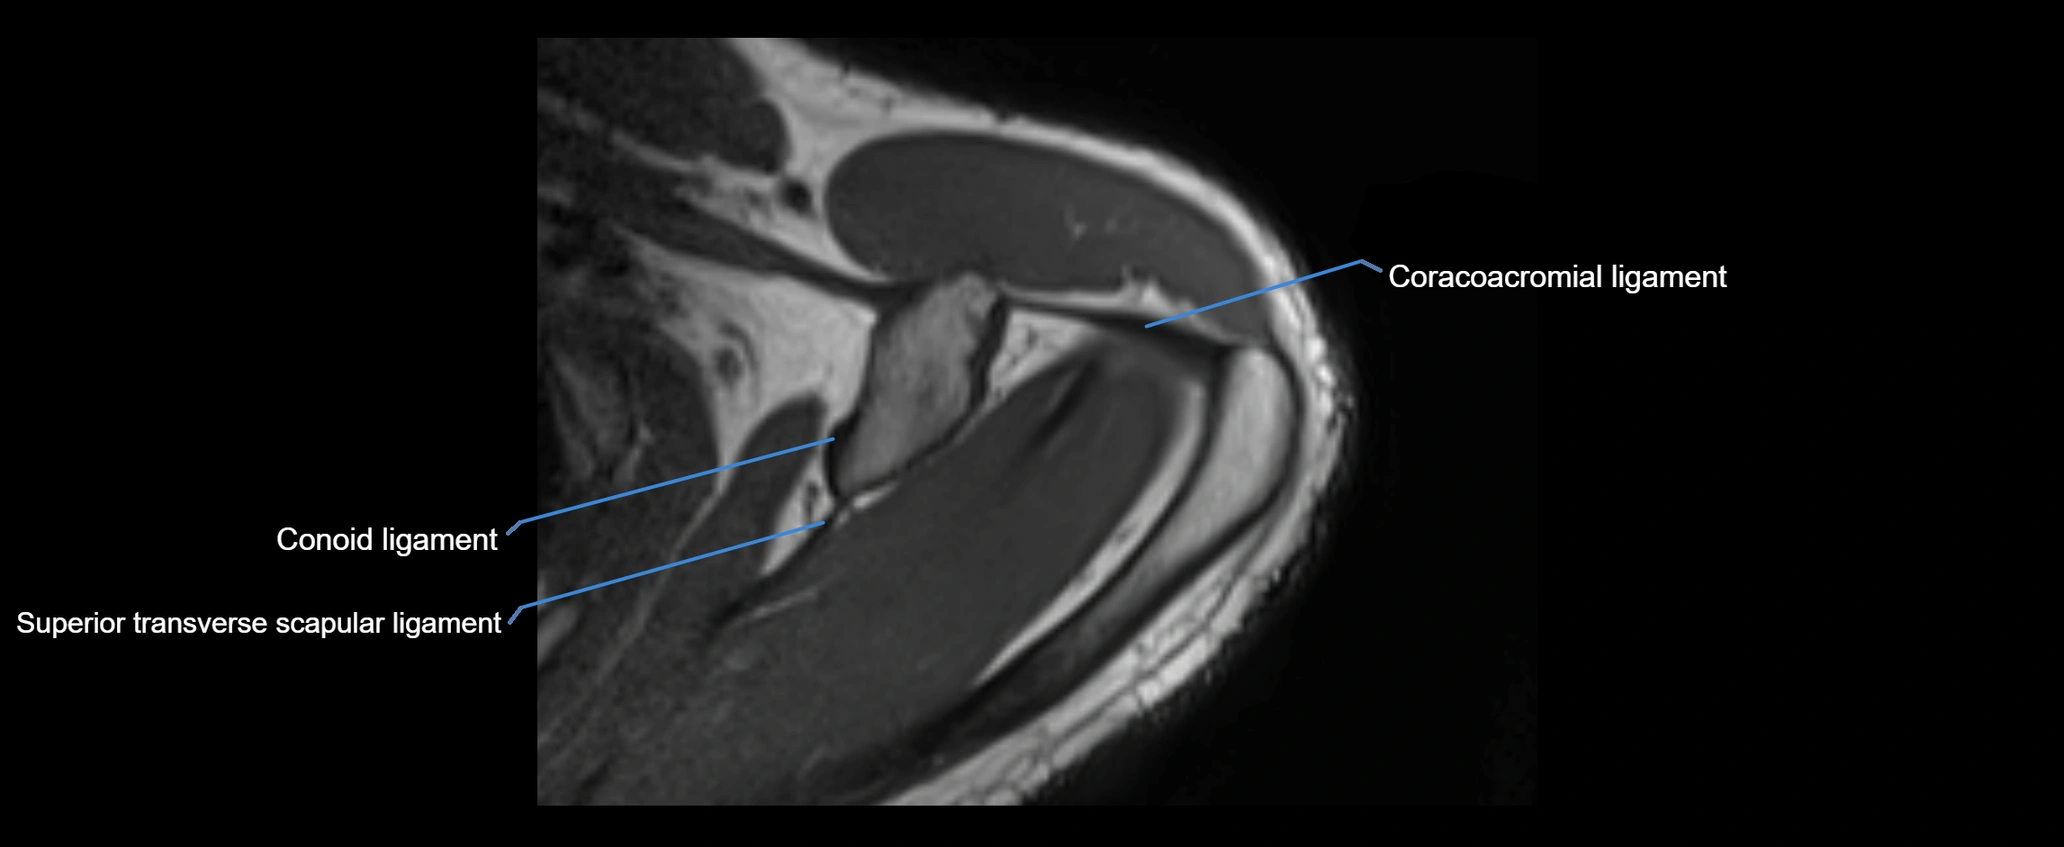

MRI images

image